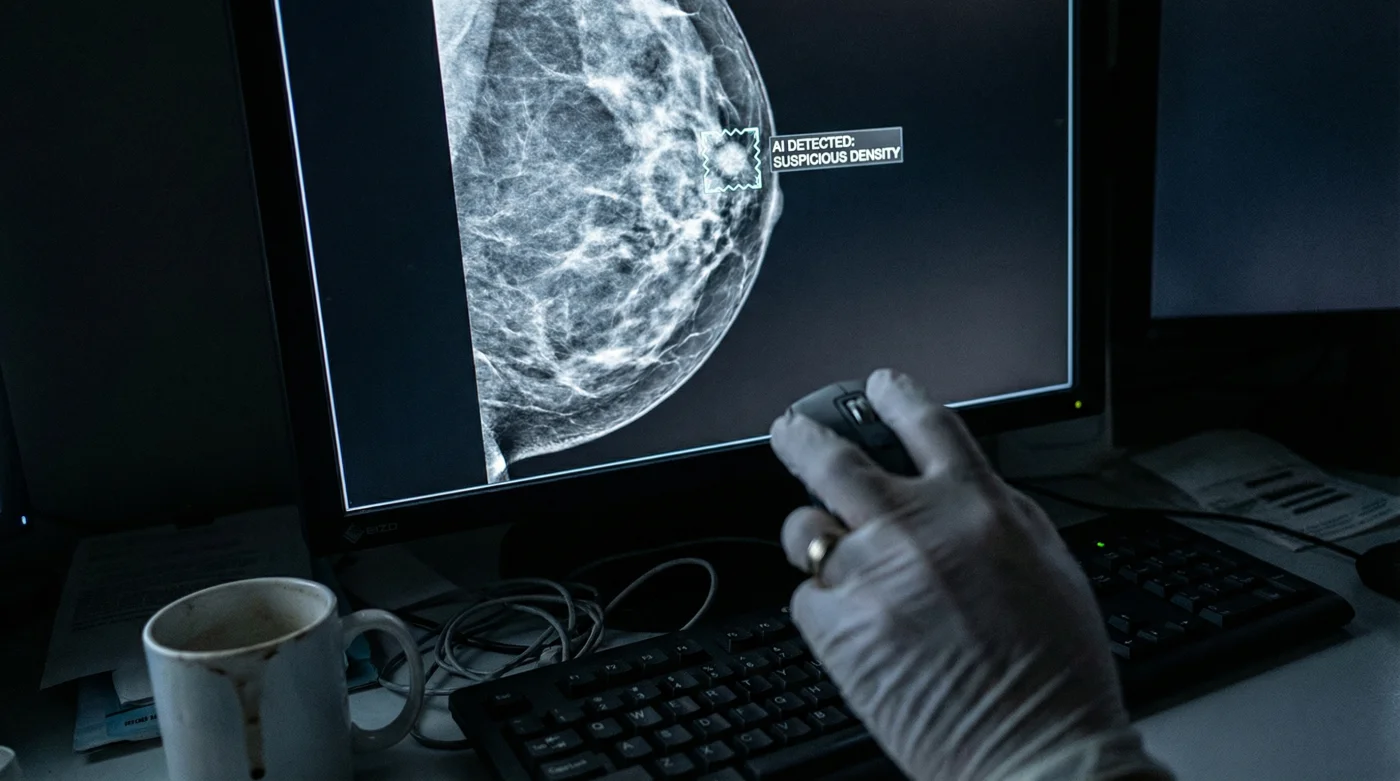

Im Zentrum dieser stillen medizinischen Revolution steht das sogenannte "Double-Check"-Protokoll. Bevor ein menschlicher Arzt überhaupt den Befund auf seinem Monitor öffnet, hat ein hochentwickelter, auf Millionen von Scans trainierter Algorithmus das Gewebe bereits in Millisekunden auf Mikroverkalkungen und kleinste Anomalien durchsucht. Die Maschine markiert Verdachtsmomente mit einer Präzision, die das menschliche Auge oft erst in einem deutlich weiter fortgeschrittenen Stadium erkennen könnte. Erst danach tritt der menschliche Facharzt auf den Plan, um die Ergebnisse der KI zu verifizieren, wodurch eine nie dagewesene diagnostische Sicherheit für Patientinnen entsteht.

- Schritt 2: Der Millisekunden-Scan: Die Künstliche Intelligenz analysiert das Gewebe umgehend auf Mikroverkalkungen, Asymmetrien und Dichteveränderungen. Sie erstellt eine visuelle Heatmap der Risikozonen für den Arzt.

- Schritt 3: Die menschliche Verifikation: Der behandelnde Radiologe prüft die von der KI markierten Areale mit seinem klinischen Fachwissen. Er bestätigt den Verdacht oder gibt die finale Entwarnung.